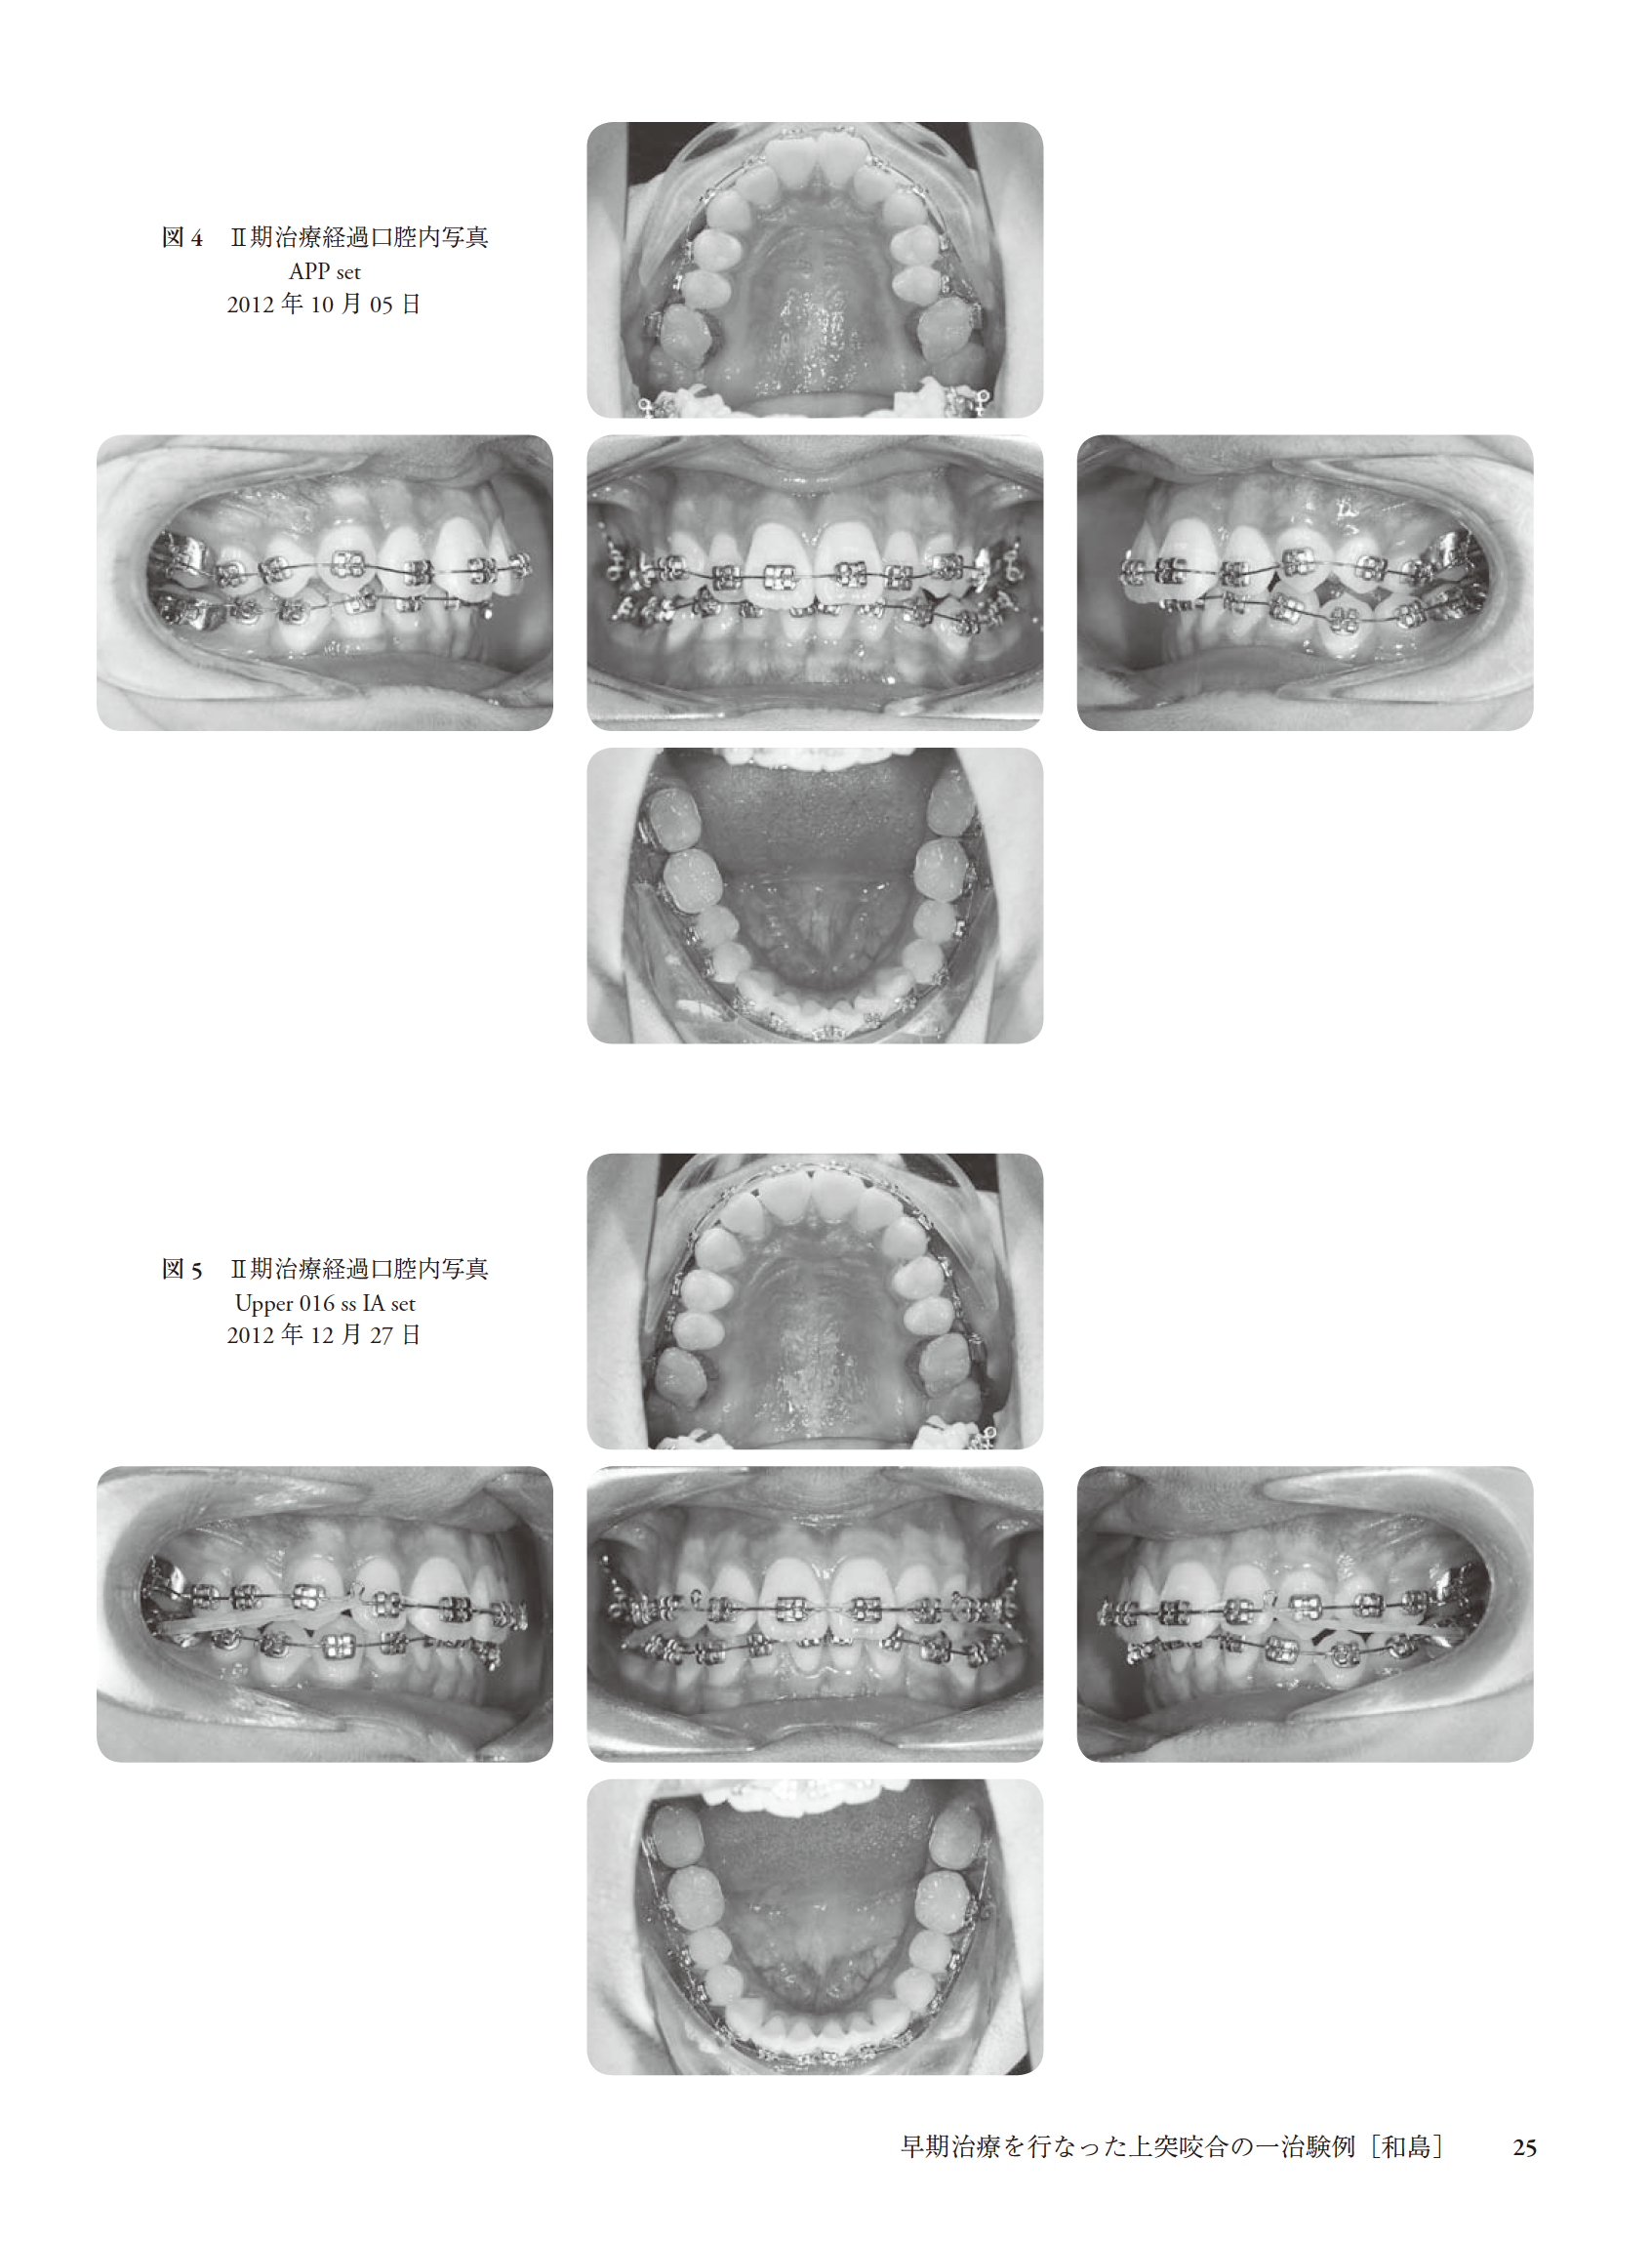

早期治療を行なった上突咬合の一治験例(和島)